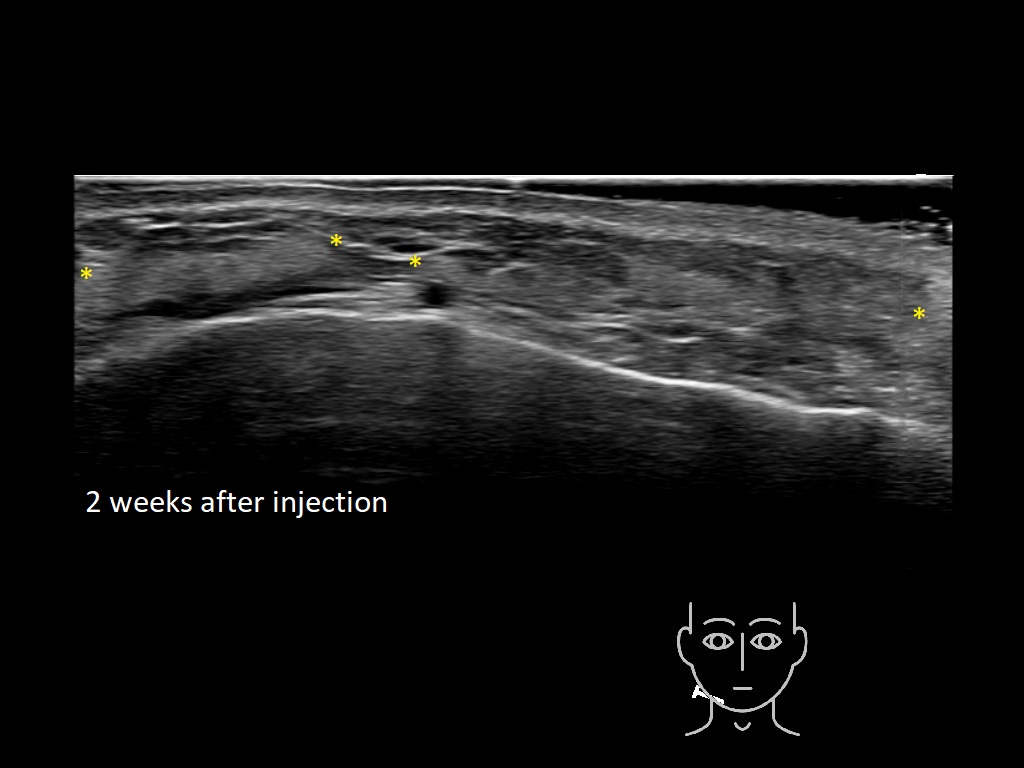

Draw in the second image below where the fillers are located. To check if your answer is correct, swipe the first image to the right.